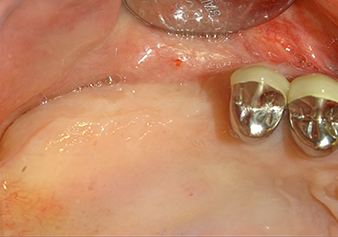

A periosteal elevator is used to place an augmentative mixture carefully into the region of the internal maxillary sinus ostium in the apical direction

Fig.8: A periosteal elevator is used to place an augmentative mixture carefully into the region of the internal maxillary sinus ostium in the apical direction.

Following an intermediate check (Fig. 4) a further preparation step was performed (Fig. 5). Afterwards, the hydraulic Z35P instrument was used to lift the membrane to the desired position (Fig. 6 and 7). This was followed by further piezosurgical preparation of the implant bed, concluded with a rotary bur and shoulder milling cutter up to the implant diameter of 4.8 mm. Before the implant was inserted, the augmentation material (particle size approx. 0.8-1.6 mm) was introduced underneath the Schneiderian membrane (Fig. 8).